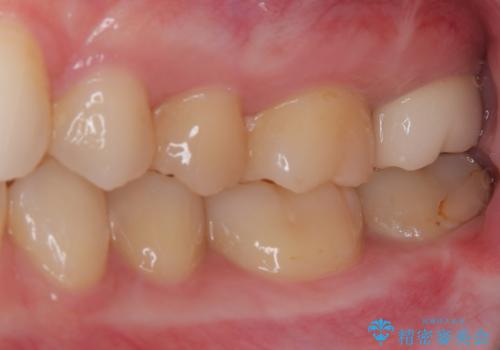

- 奥歯に激痛が走り近医を受診したところ、根管治療が必要とのことで、当院での治療を希望して来院された患者様です。

奥歯2歯の間からむし歯が広がったようで、最後方歯は既に神経が失活している状態で、手前の歯は神経組織に問題はないものの速やかに処置が必要な状態でした。

最後方歯は根管治療を行った上でオールセラミッククラウンにて補綴治療を行うこととし、手前の歯はセラミックインレーにて修復治療を行うこととしました。

当院に来院された時には既に痛みはなく、治療終了までスムーズに進めることができました。

今後は定期的にレントゲン写真を撮りながら、根管治療の経過観察を行っていくことになります。